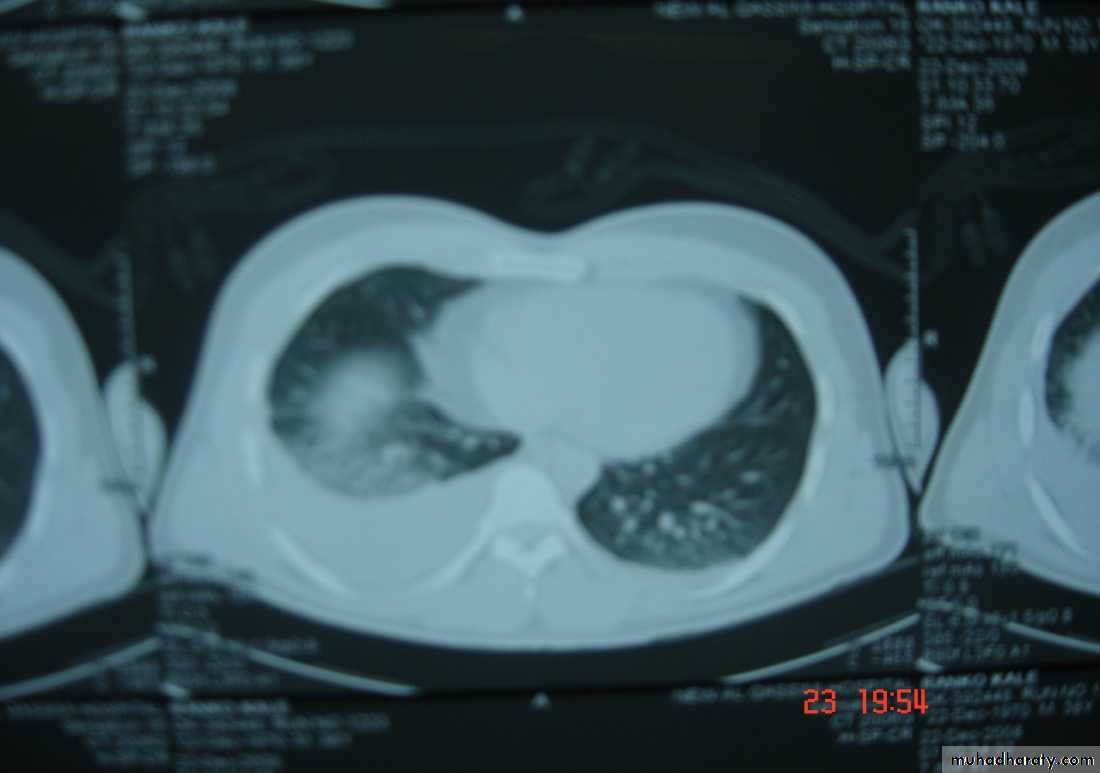

• 4-Pulmonary injuriesTrauma can lead to pulmonary contusion with interstitial edema which may lead to consolidation of the lung tissues and can be manage by antibiotics administration and clearing of secretion